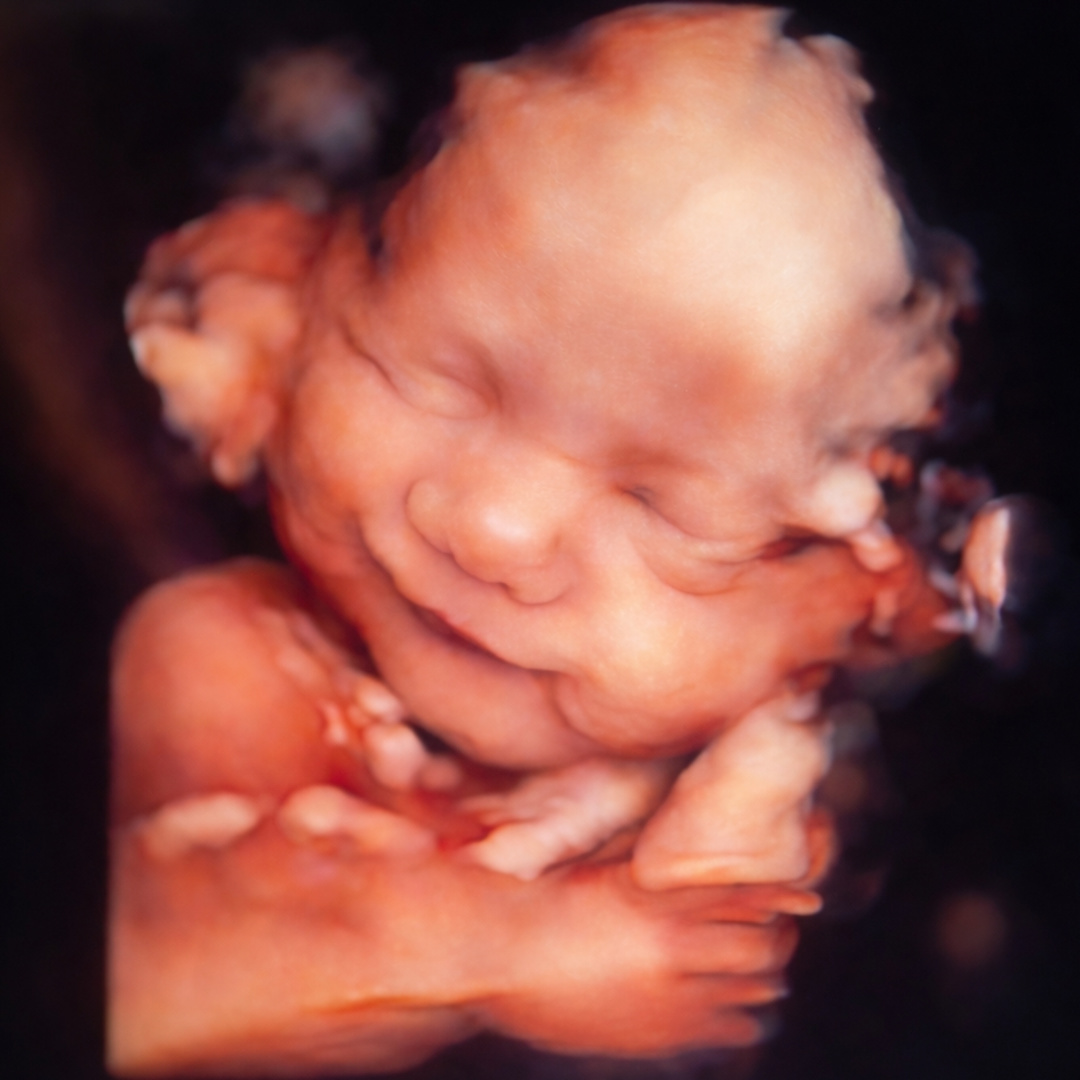

Karla and Erick's Baby Registry

Karla Salazar & Erick Acosta

May 6, 2026